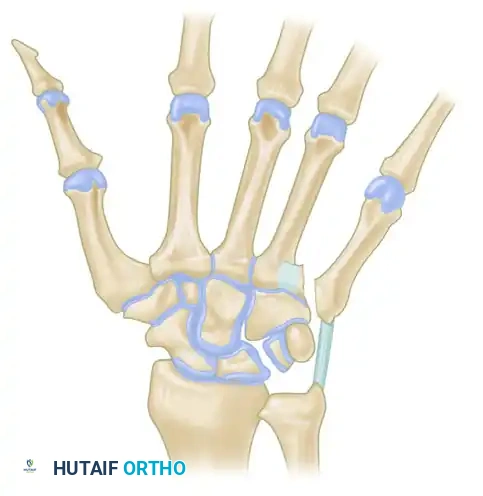

FIGURE 67-33: Kaplan open reduction of dislocation of the second metacarpophalangeal joint. The diagram illustrates the four structures that surround and constrict the metacarpal head: the volar plate, natatory ligament, superficial transverse metacarpal ligament, and the lumbrical/flexor tendon complex.

Understanding the pathoanatomy is critical. When the index finger MCP joint dislocates dorsally, the metacarpal head is driven volarly through the weakest point of the joint capsule. It becomes trapped in an anatomical "noose" composed of four distinct structures:

1. Volar Plate: Displaced dorsally over the metacarpal head, blocking reduction.

2. Natatory Ligament: Tightens distally across the metacarpal neck.

3. Superficial Transverse Metacarpal Ligament: Constricts proximally.

4. Lumbrical Muscle and Flexor Tendons: The lumbrical displaces radially, and the flexor tendons displace ulnarly, tightly flanking the metacarpal neck.